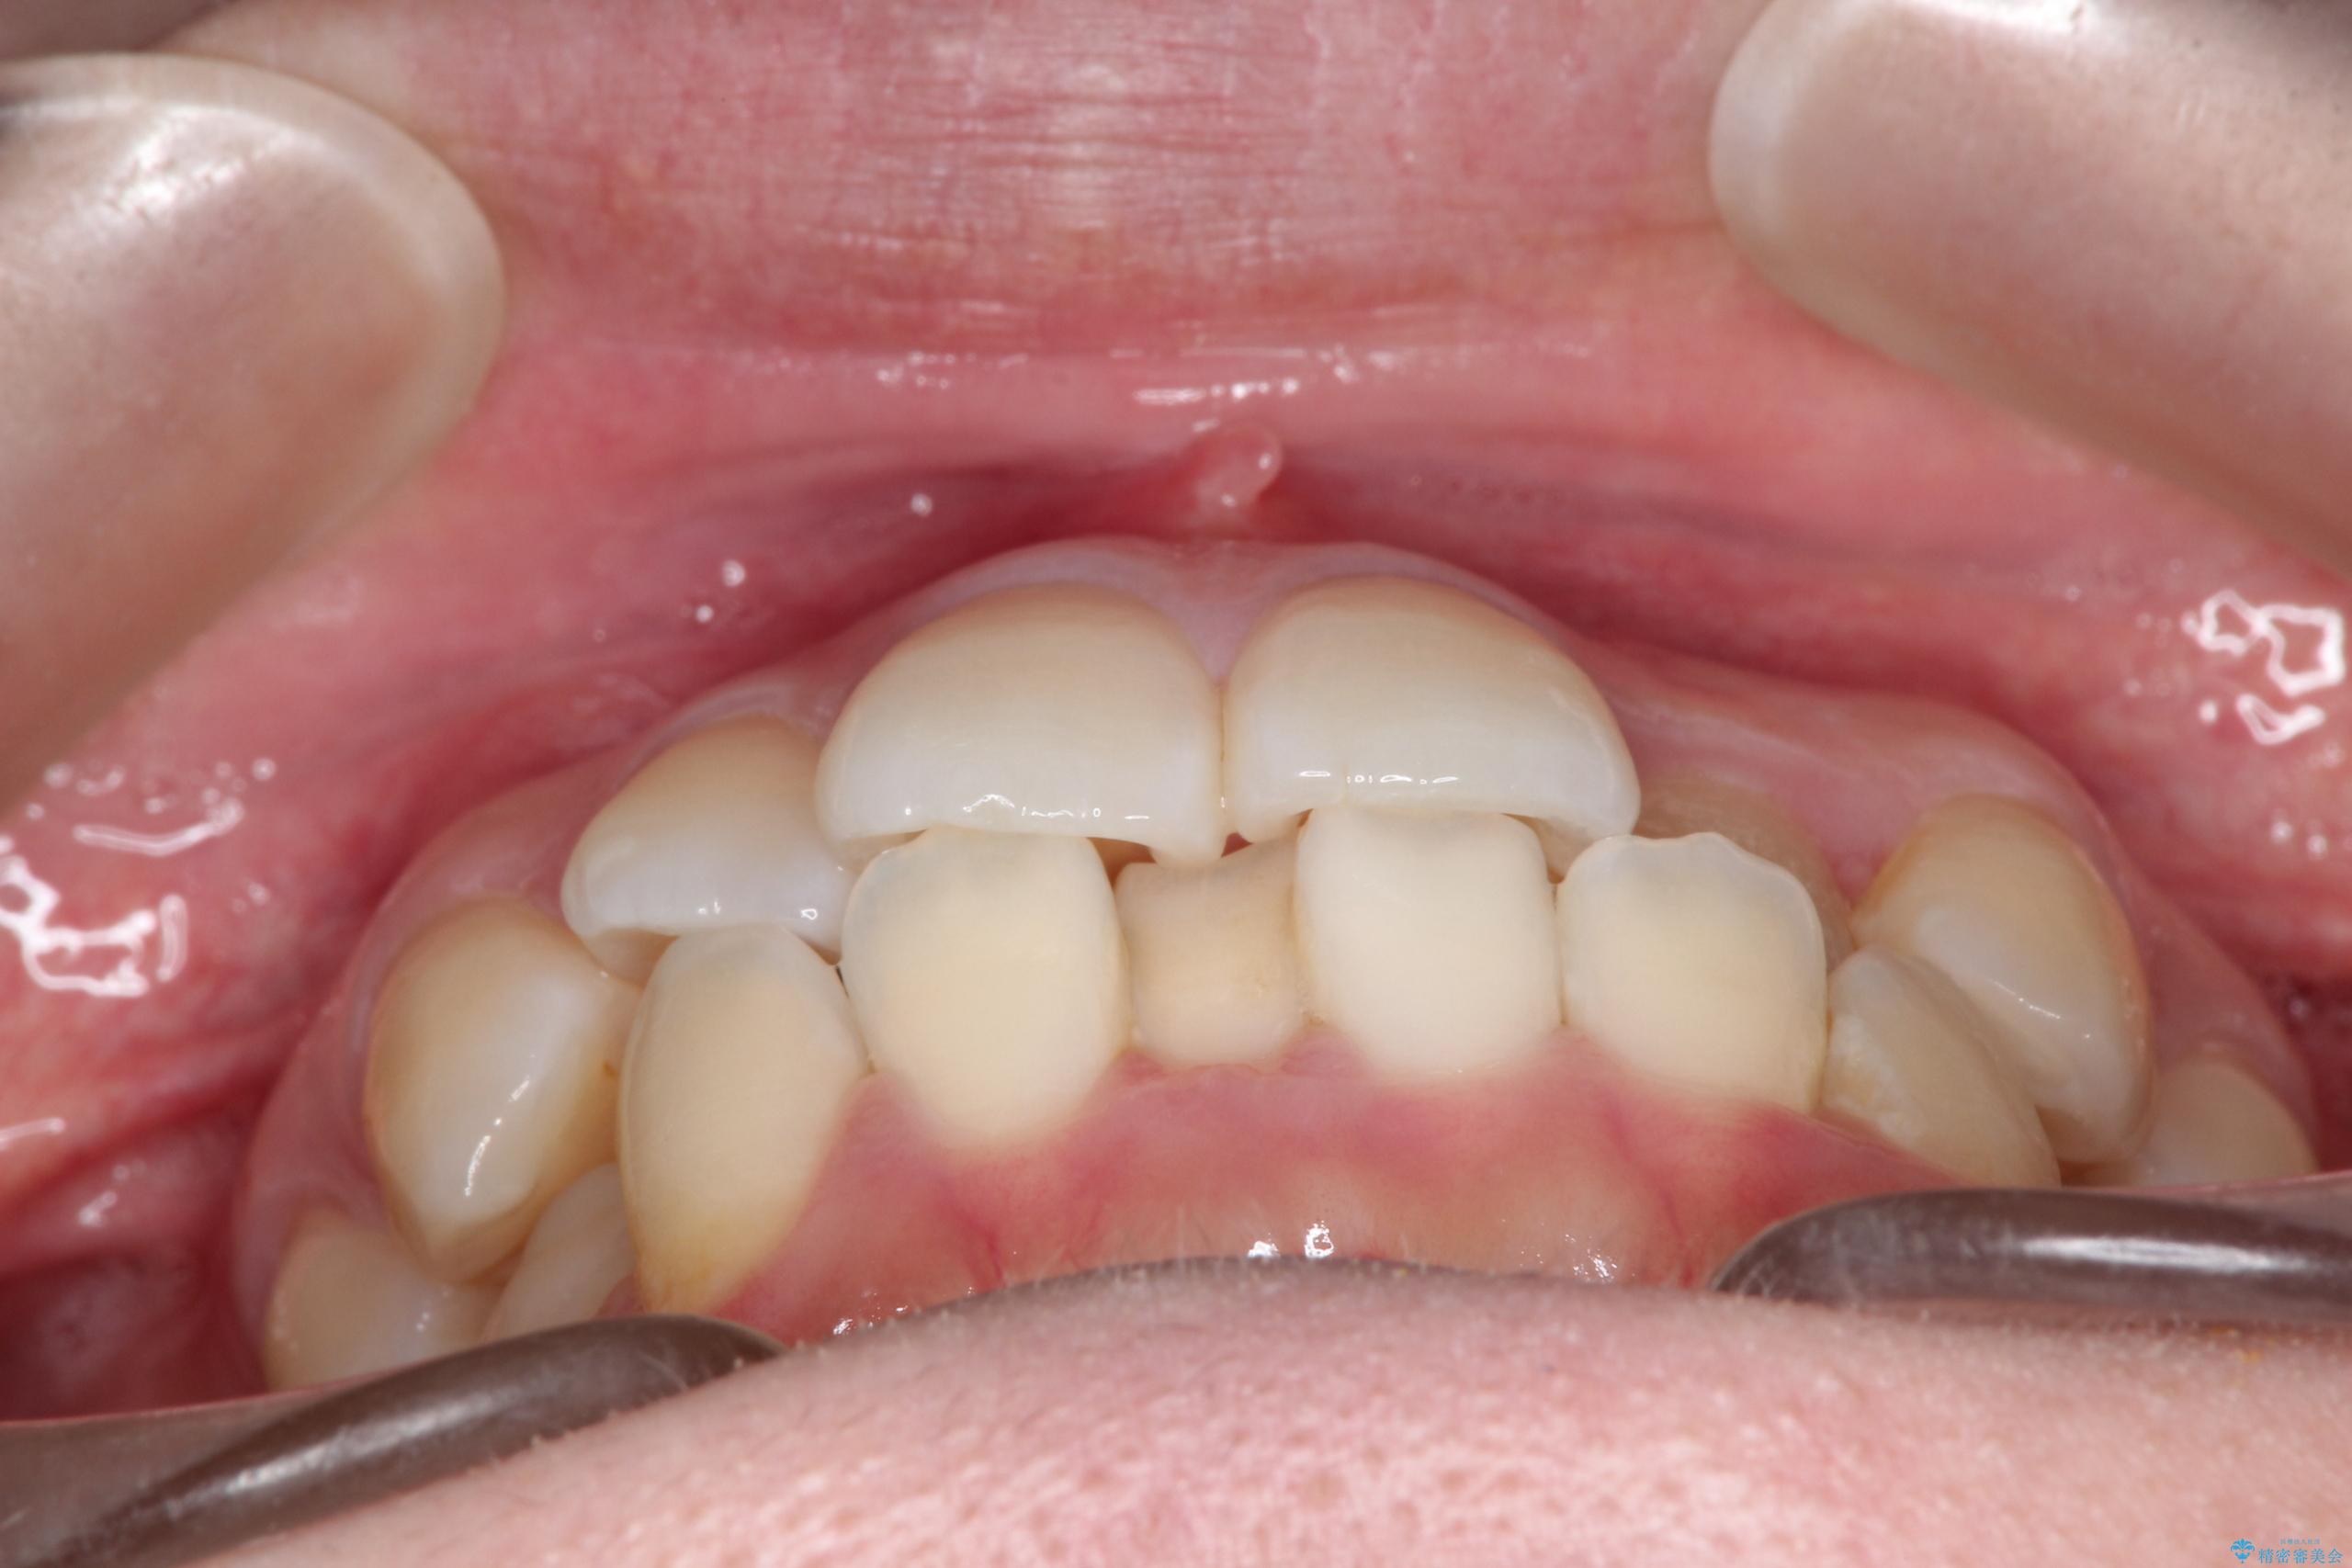

- 主訴:口元を下げて前突感を無くしたい、下の歯の凹凸も無くしたい

右側第二小臼歯、左側第一小臼歯、下顎両側第一大臼歯を抜歯しワイヤ-矯正を行いました。

骨格的顎の変位を認めたため、顔貌に対しピッタリ上下の歯の正中を合わせることは難しいと説明し、上下左右計4本小臼歯を抜歯しワイヤー矯正治療を行いました。